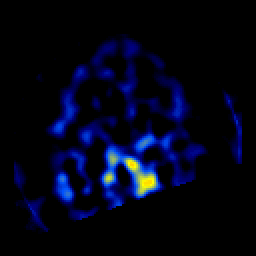

SPECT TL Study #4 -- Slice #43

[Home][Help][Clinical][Tour 1][Tour 2][Tour 3] Slice 43